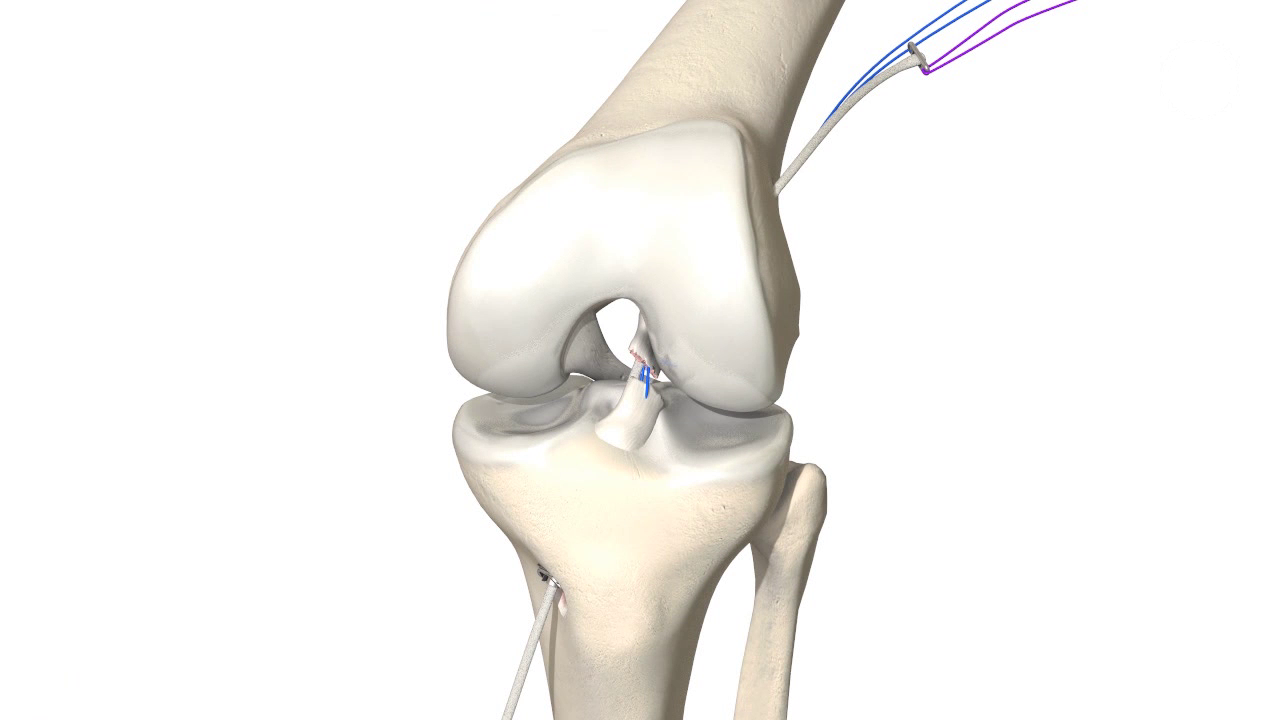

Kreuzbanderhalt durch dynamische intraligamentäre Stabilisierung (DIS) mittels Ligamys® System.

Ist das Kreuzband vollständig abgerissen ist eine Heilung ohne Operation nicht möglich. Um das Kreuzband dennoch zu erhalten kommt die Ligamys® Technik oder „Dynamische Intraligamentäre Stabilisierung“ zum Einsatz. Hierbei wird das abgerissene Kreuzband über eine wenig Millimeter messende Bohrung mit Nähten wieder am Oberschenkelknochen fixiert. Um die Naht in der Zeit der Heilung zu schützen wird eine stabile Kordel als innere Schienung parallel zum Kreuzband gespannt. Diese Kordel wird im Unterschenkelknochen im eigentlichen Ligamys® Implantat verankert. Hier sorgt eine Feder dafür, dass die Kordel über das gesamte Bewegungsausmaß die selbe Spannung behält. Der gesamte Eingriff wird im Rahmen einer Kniegelenksspiegelung also ohne weite Eröffnung des Kniegelenks durchgeführt.

Nach der Operation wird das Kniegelenk für 5 Tage entlastet und in einer Schiene ruhiggestellt. Anschließend kann das Bein voll belastet und frei beübt werden. Eine Schiene ist nicht erforderlich.